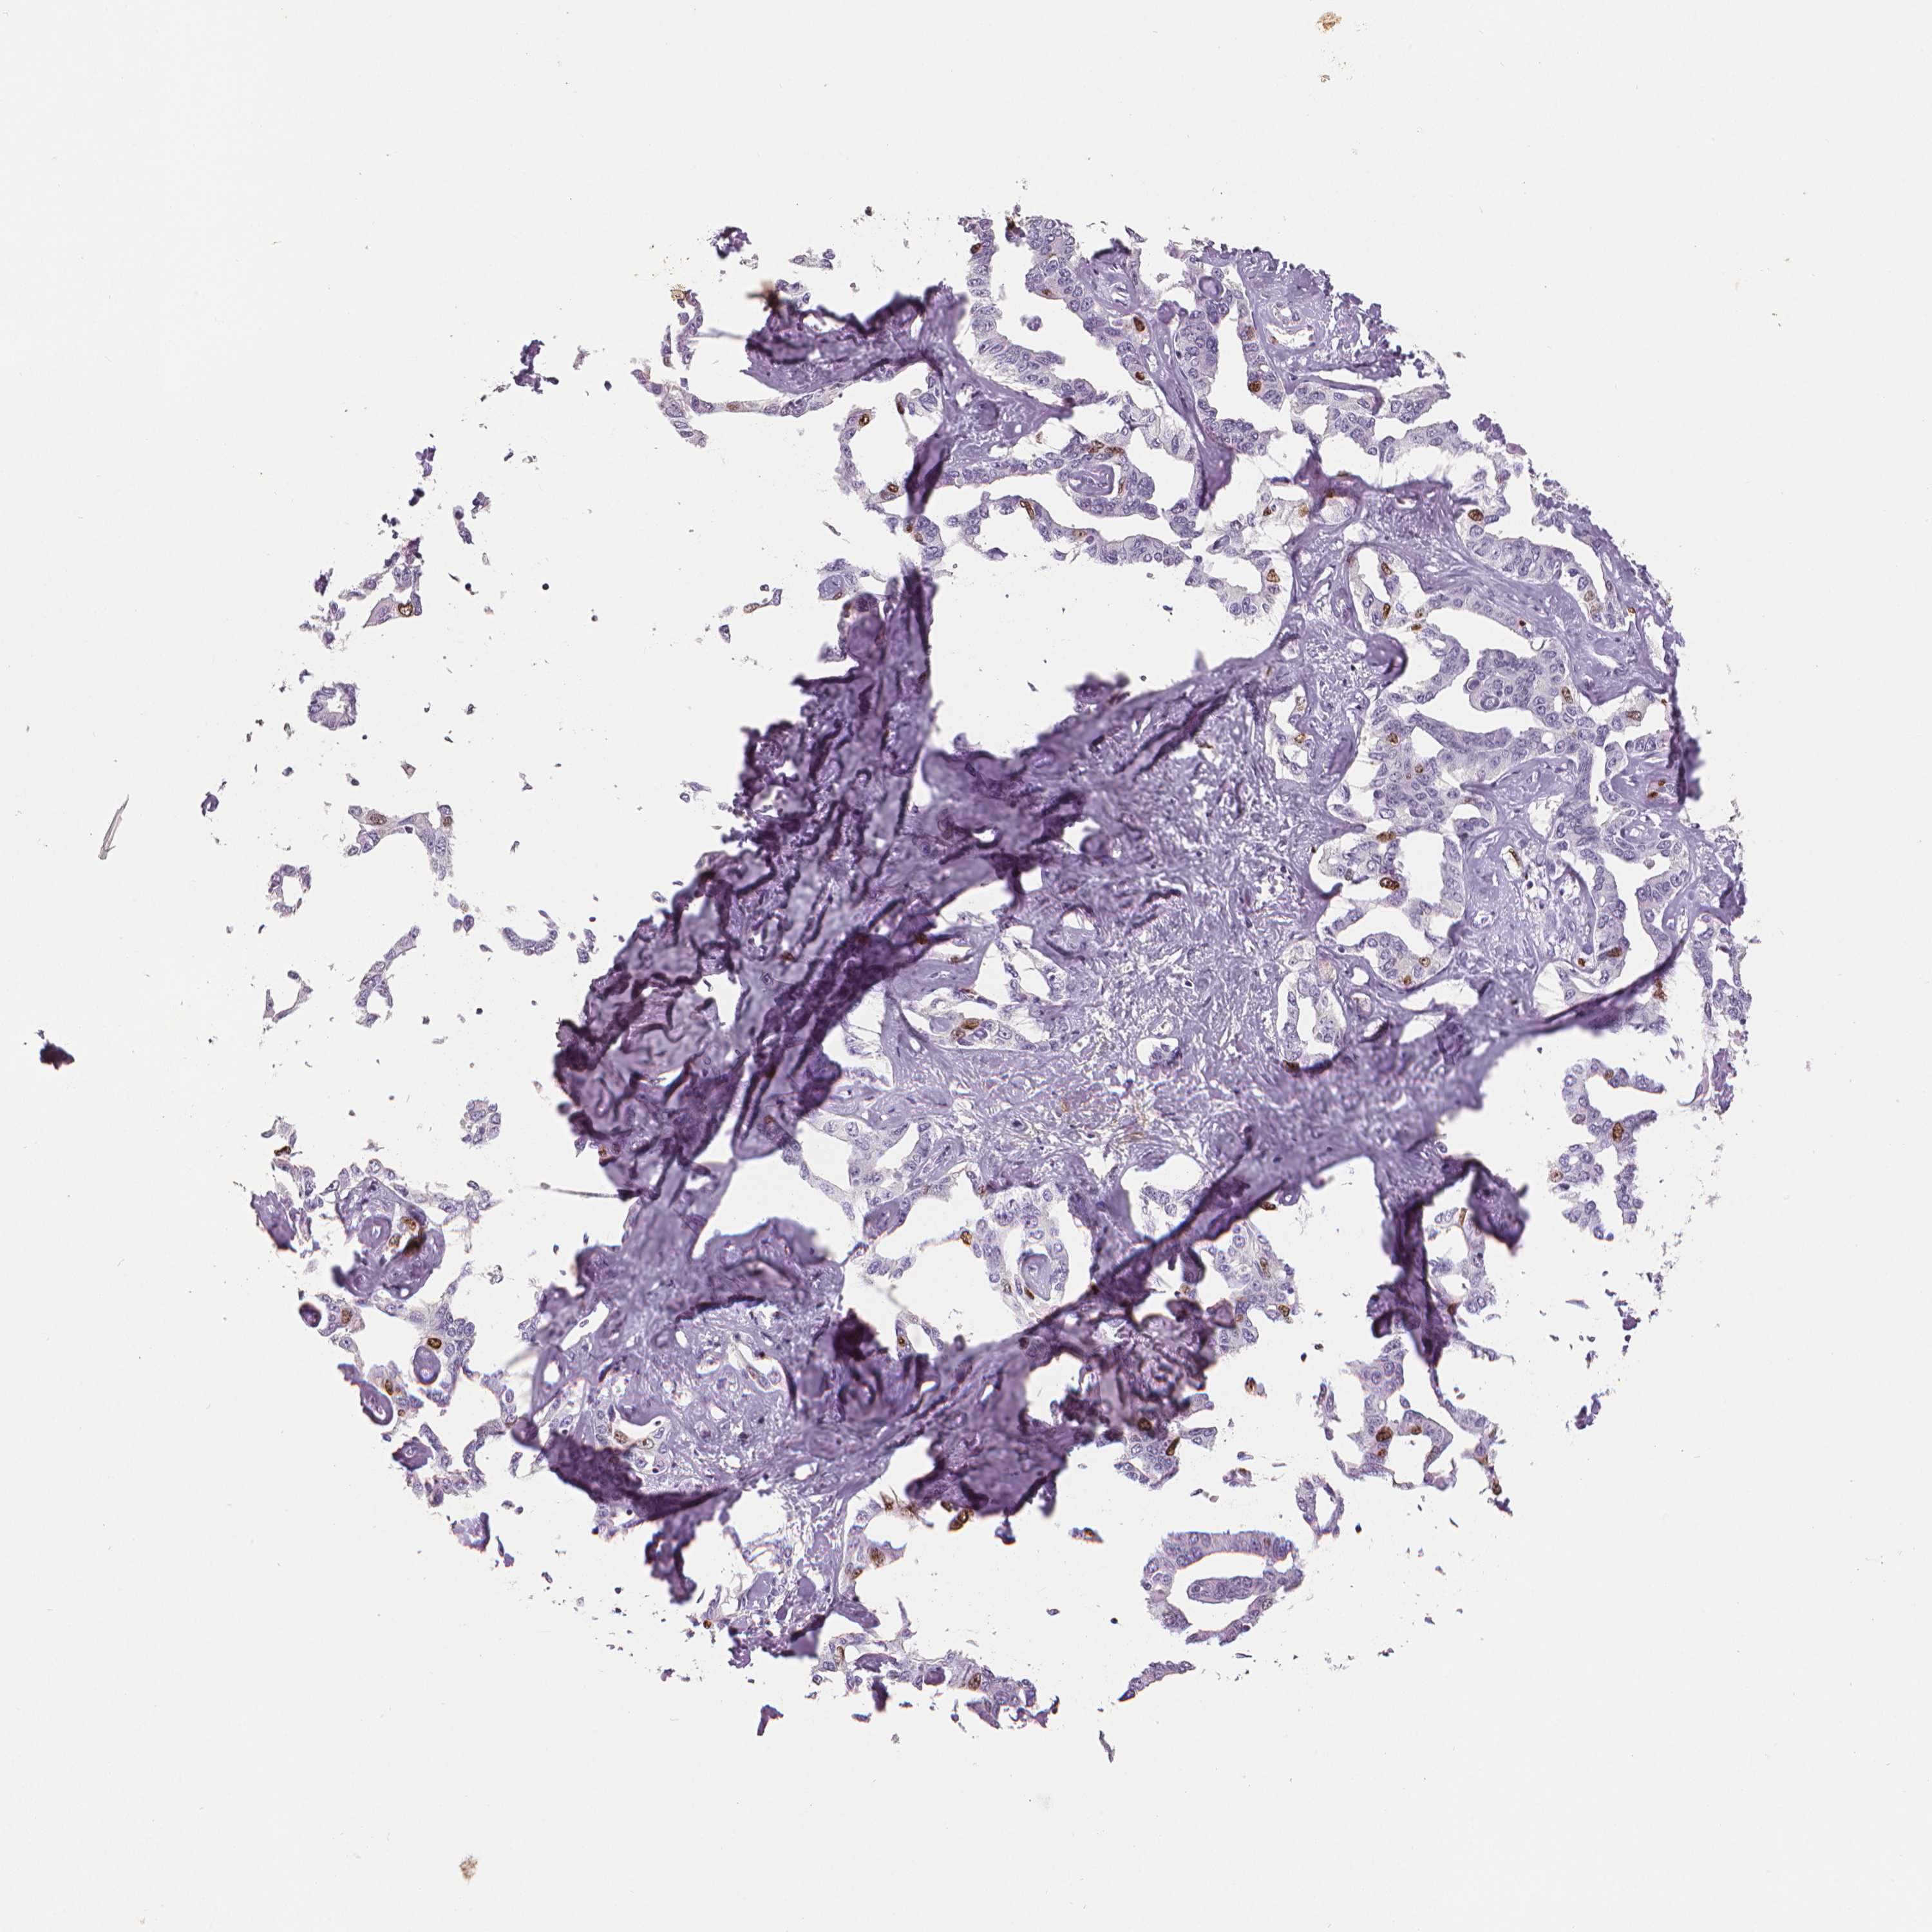

LIVER CANCER - Protein expressioni

A mouse-over function shows sample information and annotation data. Click on an image to view it in a full screen mode. Samples can be filtered based on level of antibody staining by selecting one or several of the following categories: high, medium, low and not detected. The assay and annotation is described here.

Note that samples used for immunohistochemistry by the Human Protein Atlas do not correspond to samples in the TCGA dataset.

Antibody stainingi

Antibody staining in the annotated cell types in the current human tissue is reported as not detected, low, medium, or high, based on conventional immunohistochemistry profiling in selected tissues. This score is based on the combination of the staining intensity and fraction of stained cells.

Each image is clickable and will lead to virtual microscopy that enables deeper exploration of all samples and also displays staining intensity scores, fraction scores and subcellular localization as well as patient and tissue information for each sample.

Carcinoma, Hepatocellular, NOS

Cholangiocarcinoma